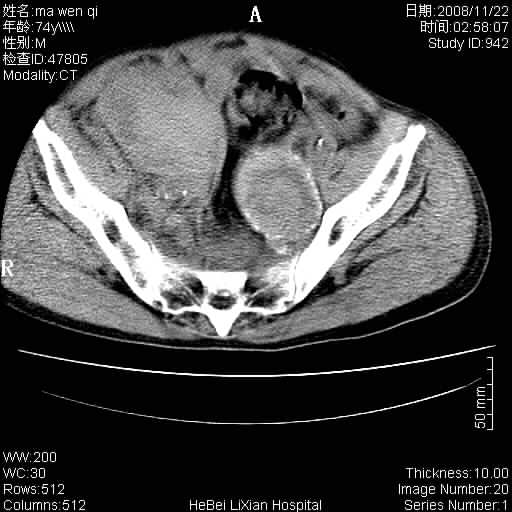

患者男 74岁.突然昏迷,休克6小时.血压70/30,头颅ct未见异常,既往体健.

补充病史,保留导尿10小时,尿袋内只有少许尿液,患者于住院后15小时后去世.

腹主动脉、双侧髂动脉夹层动脉瘤破裂出血进入腹腔。

考虑双侧髂a瘤,伴破裂出血

腹主动脉、双侧髂动脉夹层或动脉瘤破裂出血进入腹腔

1)考虑双侧髂动脉瘤并右侧动脉瘤破裂出血,右侧腹膜后及腹腔积血。2)双侧腹股沟疝。

支持(1)双侧髂动脉瘤并右侧动脉瘤破裂出血,右侧腹膜后及腹腔积血。(2)双侧腹股沟疝。

1)考虑,腹主动脉、双侧髂动脉夹层动脉瘤破裂伴右侧腹膜后及腹腔积血。2)双侧腹股沟疝。

1)考虑胸、腹主动脉、双侧髂动脉瘤并右侧动脉瘤破裂出血,右侧腹膜后及腹腔积血。2)双侧腹股沟疝。